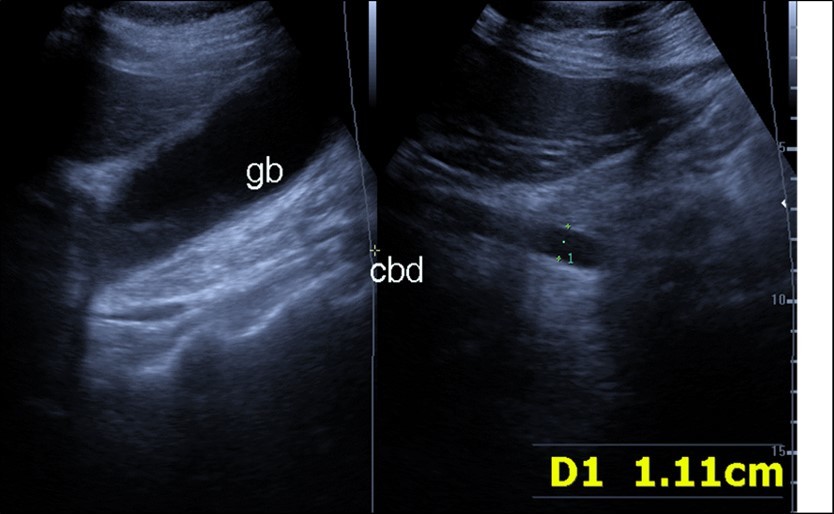

Abdominal ultrasound may revealed any of the followings:-Mild hepatomegaly with echogenic parenchyma and ascites in cases with hepatic impairment (Figure 4, Figure 5) ,thick walls of gall bladder with mildly dilated Common bile duct suggesting of biliary stasis and cholecystitis (Figure 6) .Abnormal renal echogenicity (Figure 7), suprarenal gland enlargements with heterogeneous texture ,splenic wedge shape area of hypoechogenicity ,thickened walls of bowel mainly the rectosigmoid region ,dilated bowel loops with free peritoneal fluid, and gases in the bowel wall with mesenteric and portal vein gases suggesting of bowel wall infarction13.

Figure 4.Real time ultrasound showing thickened wall of gall bladder (gb) with dilated Common bile duct (cbd) in patient with severe Covid-19.

Real time ultrasound showing thickened wall of gall bladder (gb) with dilated Common bile duct (cbd) in patient with severe Covid-19.